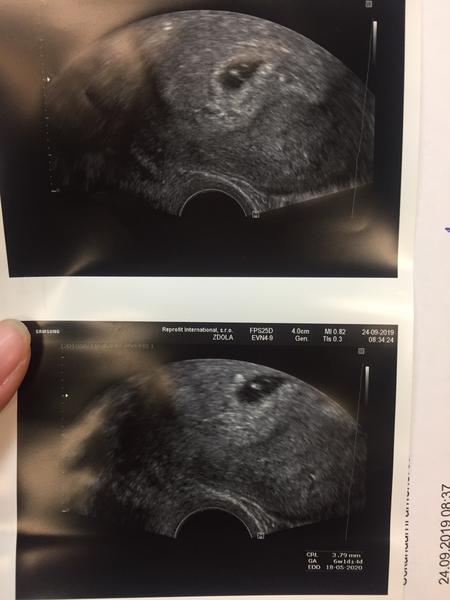

@maminka2020 Tak já měla dva týdny zpět úplně stejný obrázek (prázdný gestační váček - 5. týden). Objednali mě moc brzy a dva týdny jsem se zbytečně stresovala. Min. týden jsem byla na kontrolním ultrazvuku a bylo tam krásně vidět i srdíčko. Prostě jsem měla ovulaci později. Držím pěsti, ať to dobře dopadne.

@maminka2020 Mám z 6+2